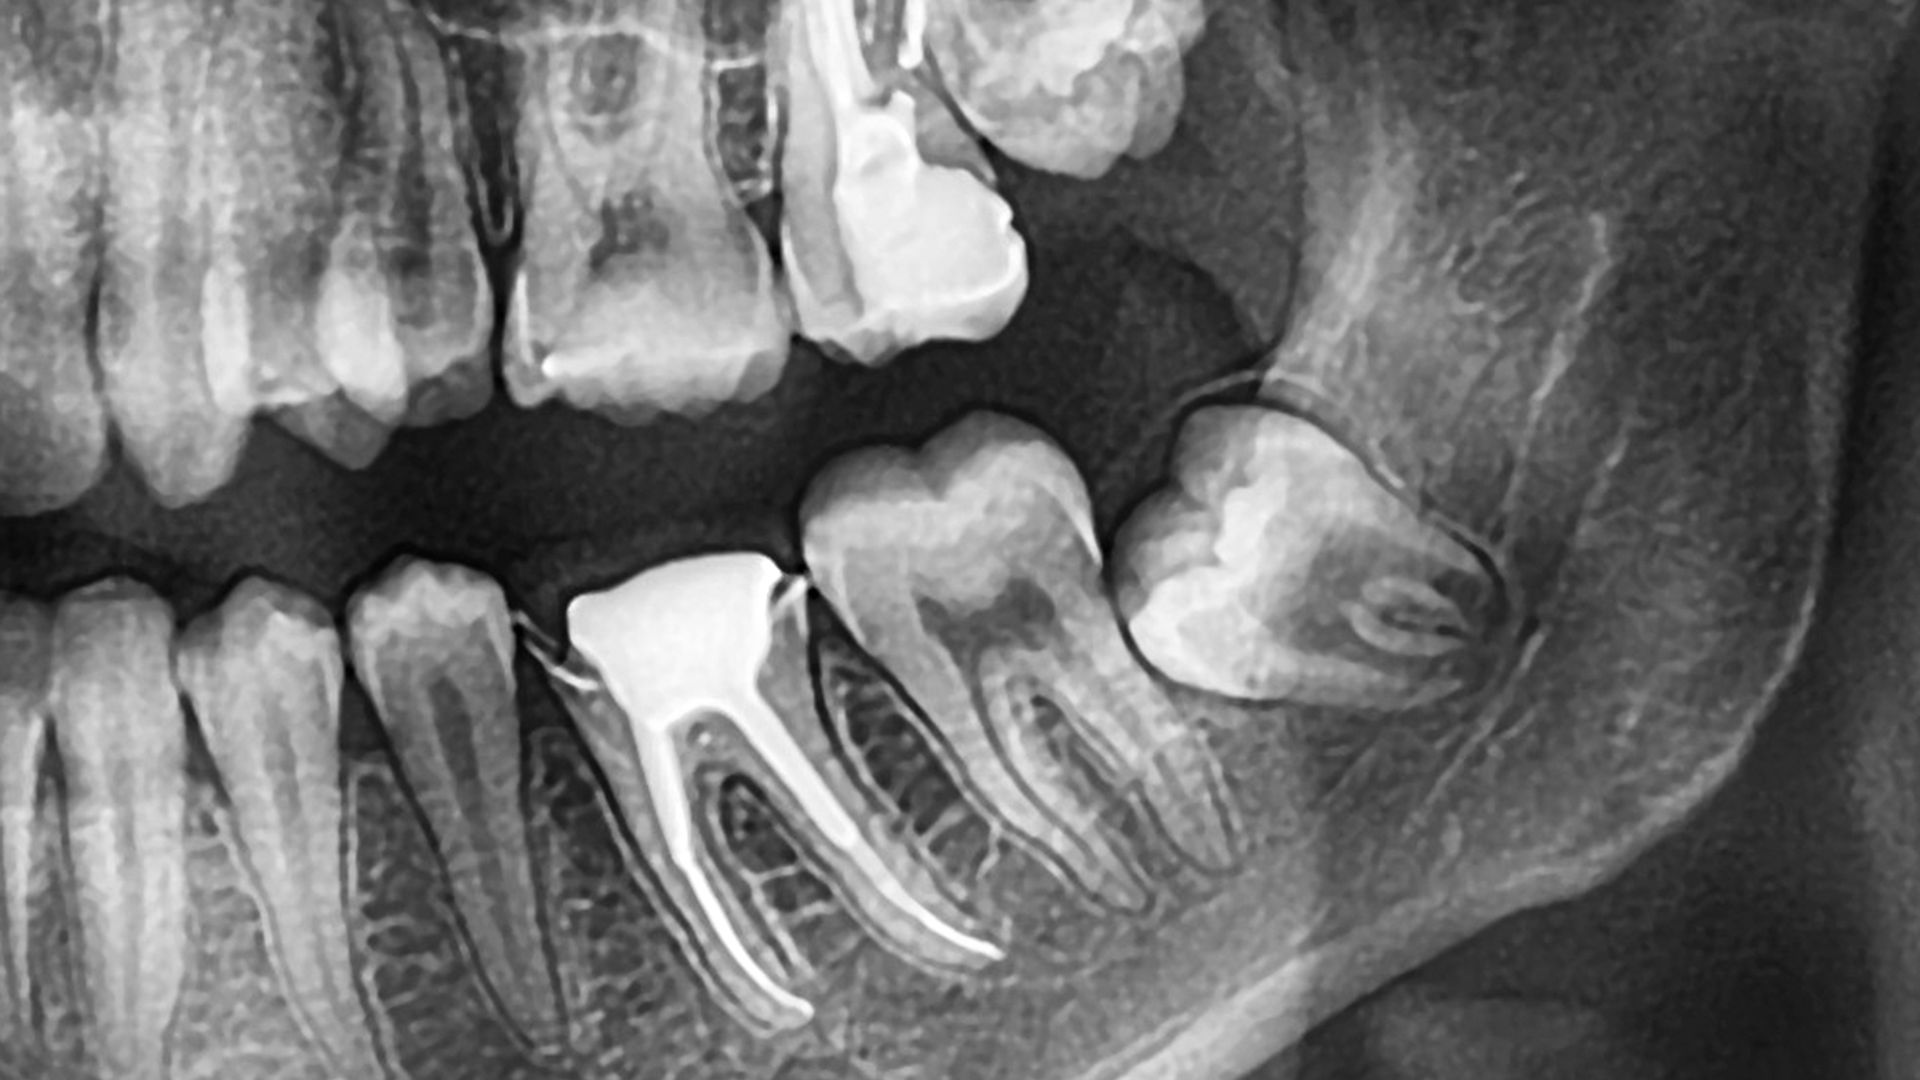

Wisdom teeth extractions in Compton often become necessary when back molars cause pain, swelling, or repeated infection. Many local patients delay care until discomfort disrupts daily life. As a result, untreated wisdom teeth frequently lead to gum disease, damage to nearby molars, and jaw complications. The American Dental Association explains how impacted and partially erupted wisdom teeth commonly cause infection and crowding, especially when removal is delayed. At PhD Dental, we provide wisdom tooth removal for Compton residents who want clear answers and decisive care. Because wisdom teeth often erupt improperly, we focus on early diagnosis and careful planning. Therefore, our approach helps limit recovery time while protecting surrounding teeth and bone. We also serve families throughout nearby areas shown on Google Maps, including neighborhoods near South Long Beach Boulevard and the Compton Civic Center. This local access allows patients to receive timely follow up care after extractions. Wisdom teeth removal in Compton should never feel rushed or uncertain. Instead, we explain each step before treatment begins and outline what to expect during healing. Our team uses advanced imaging to evaluate root position and nerve proximity, which supports safer outcomes.

Wisdom teeth extractions in Compton are frequently recommended because third molars rarely erupt in a way that supports long term oral health. These teeth develop later than all other permanent teeth and must fit into a jaw that has already completed most of its growth. As a result, wisdom teeth often emerge at awkward angles or remain trapped beneath the gums. When this occurs, pressure builds behind the second molars and creates ongoing discomfort that does not resolve on its own.

Jaw growth plays a major role in why wisdom teeth extractions in Compton are so common. During adolescence, the jaw finishes expanding while wisdom teeth continue developing beneath the surface. By the time these molars attempt to erupt, there is often insufficient space remaining. This mismatch between tooth size and available room leads to impaction and misalignment.

Timing plays a critical role in wisdom teeth extractions. Younger patients typically experience smoother procedures and faster recovery because bone remains more flexible and roots are not fully established. As patients age, jawbone density increases and roots become more firmly anchored.

Denser Jawbone Adds Surgical Challenges Over Time

Imaging performed before infection develops allows careful assessment of root position and nerve proximity. This information guides safer extraction and smoother healing. Patients who act early often avoid emergency complications entirely.